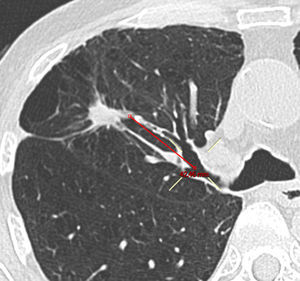

Datos de imagenUn radiólogo especializado en imágenes torácicas se encargó de revisar la última TAC torácica disponible e informó acerca de la morfología (opacidades sólidas, en parte sólidas o en vidrio esmerilado puras), el tamaño (eje transverso mayor) y la distancia de las LLP respecto al hilio. La distancia se calculó en imágenes reformateadas oblicuas midiendo la distancia entre el margen interno de la LPP y el origen proximal del bronquio segmentario correspondiente. La presencia de signo bronquial en la TAC se evaluó mediante imágenes axiales y reformateadas17.

El RD y el RV dependen del tamaño de la lesión: 64,0% y 80,0% respectivamente para LPP ≤20mm (n=25) y 80,8 y 84,6% respectivamente para LPP >20mm (n=26). En cuanto a otras características radiológicas de los nódulos, como distancia de la LPP a la pleura, el RV mejoró significativamente (p=0,021) solo si la distancia al hilio (fig. 2) era <50mm. Por lo que respecta al RD, no se encontró ningún factor pronóstico radiológico (tablas 2 y 3).

En el presente estudio no es posible excluir algunas de las limitaciones inherentes de un análisis retrospectivo, como un posible sesgo de selección en favor de pacientes con alto riesgo de neoplasia maligna o LPP accesibles mediante broncoscopia. No obstante, los rendimientos diagnósticos registrados aquí se ajustan a la regresión lineal entre la prevalencia de neoplasias pulmonares malignas y la sensibilidad de la R-EBUS realizada por Steinfort et al.18. Otra limitación, inherente a la mayoría de los ensayos que estudian el diagnóstico de LPP, afecta a la determinación del diagnóstico y a los criterios histocitológicos empleados para la neoplasia maligna. En nuestro estudio, la combinación de los criterios histopatológicos y el seguimiento clínico en casos dudosos no supuso ningún falso positivo. En último lugar, se utilizó un nuevo método basado en imágenes reformateadas oblicuas para calcular la distancia entre el hilio y las LPP (fig. 2). El estudio de Tay et al. introdujo el uso de la fórmula de Pitágoras para calcular la distancia de las LPP al hilio en 3D24. No obstante, con este método no se tiene en cuenta la distancia real de la ruta bronquial. En el presente estudio, las imágenes reformateadas oblicuas permitieron calcular la distancia entre el margen más interior de la LPP y el origen del bronquio segmentario afectado. De esta forma, se pudo realizar un cálculo más preciso de la ruta bronquial que debía seguirse en la intervención broncoscópica.